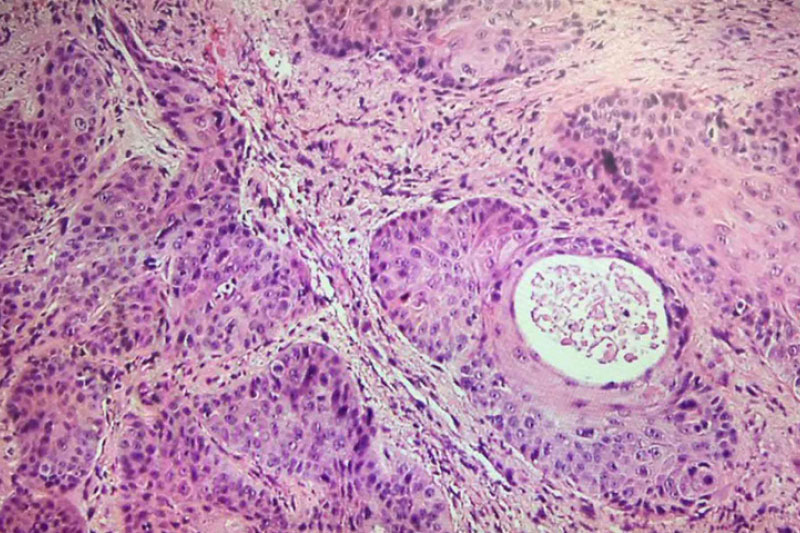

Dr. Ashley Clark is a board-certified oral pathologist currently serving as the President of CAMP Laboratory in Indianapolis, Indiana after a nearly decade-long career serving as an oral pathologist in academia. Learn More ยป